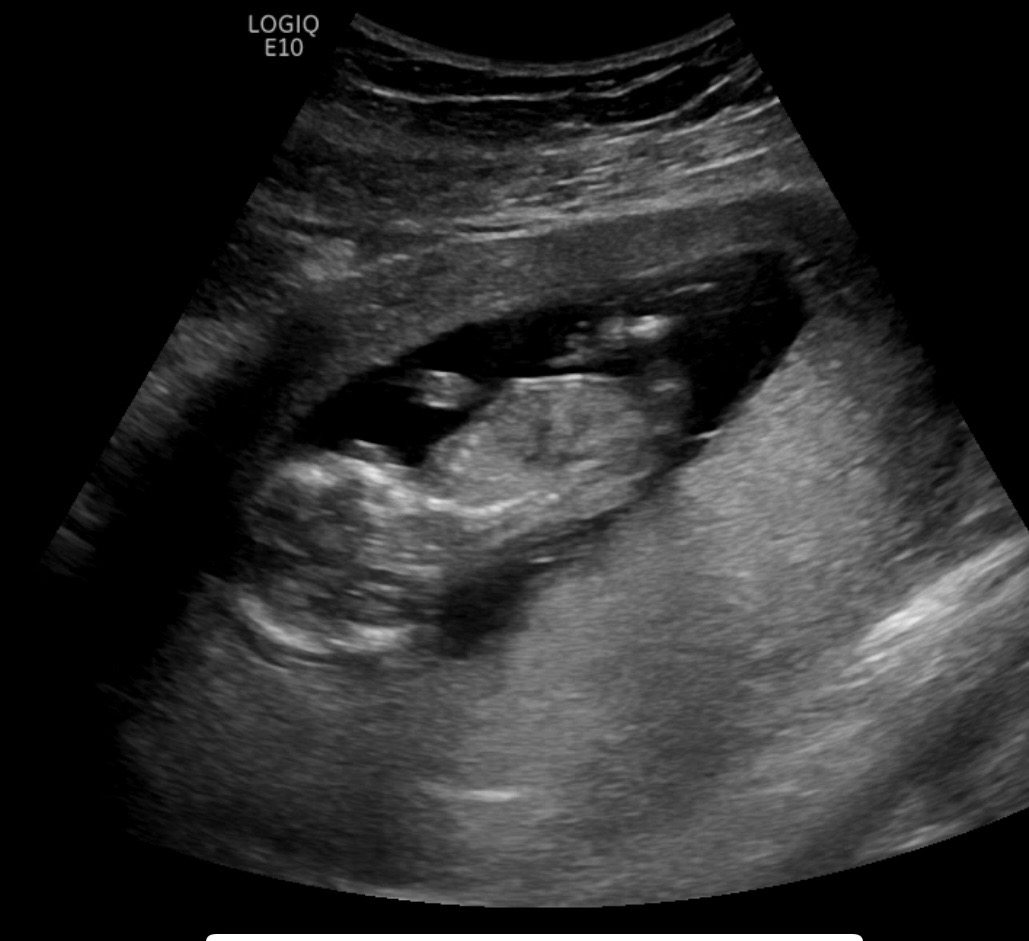

12주5일 각도법으로 성별 보일까요?!

전혀 뭔지 예상이 안되네요ㅠㅠ 각도법으로 이 사진들로도 성별 예측이 가능할까요?